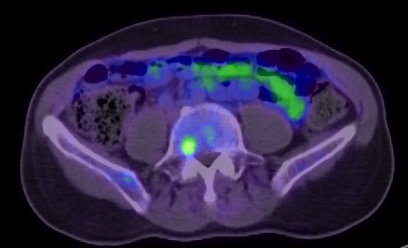

Latest example is this guy with an unfavorable, intermediate risk prostate cancer (T1c, GS4+3, PSA 14)

MRI came back completely negative. Absolutely nothing to be seen on that spot in the bone.

I am ignoring it, and treating prostate only with 4 months of ADT.

View attachment 349354